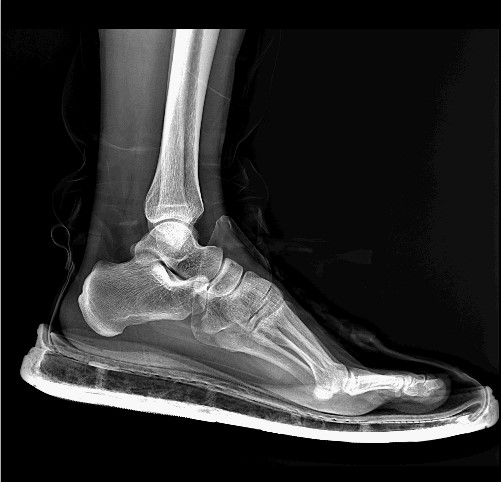

1. 高清晰度影像:便携DR能够产生高清晰度的数字化射线影像,提供更 、更详细的诊断信息,有助于医生更准确地诊断疾病。

5. 应用范围广:便携DR的应用范围非常广,可以应用于各种部位拍摄,如胸部、腹部、四肢等,能够为医生提供更多更丰富的诊断信息,适用于急诊、ICU等多种临床环境。